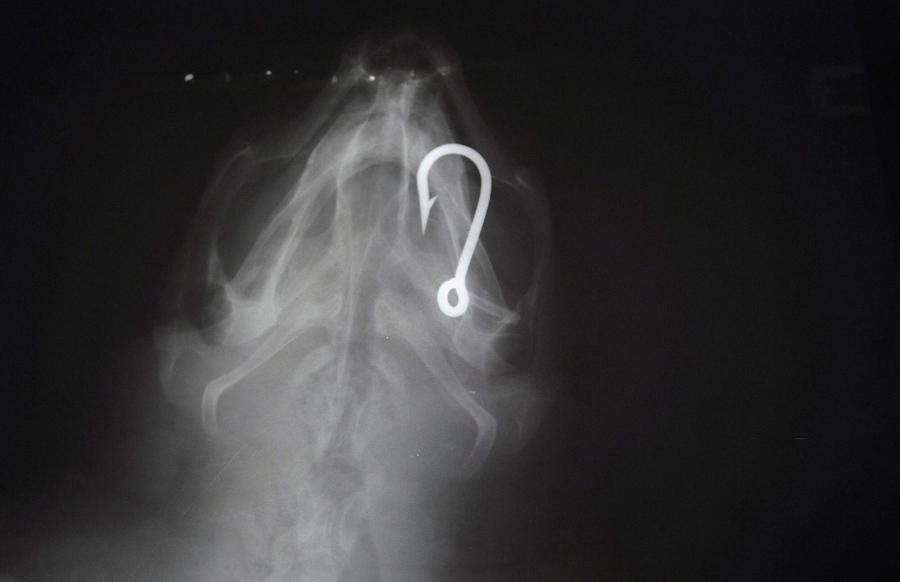

An X-ray shows a hook in the body of a turtle at the Lampedusa Turtle Rescue Center, which takes care of turtles accidentally captured with longline hooks or trawling nets, on October 12, 2015, on the island of Lampedusa, Italy.Mario Laporta / AFP / Getty